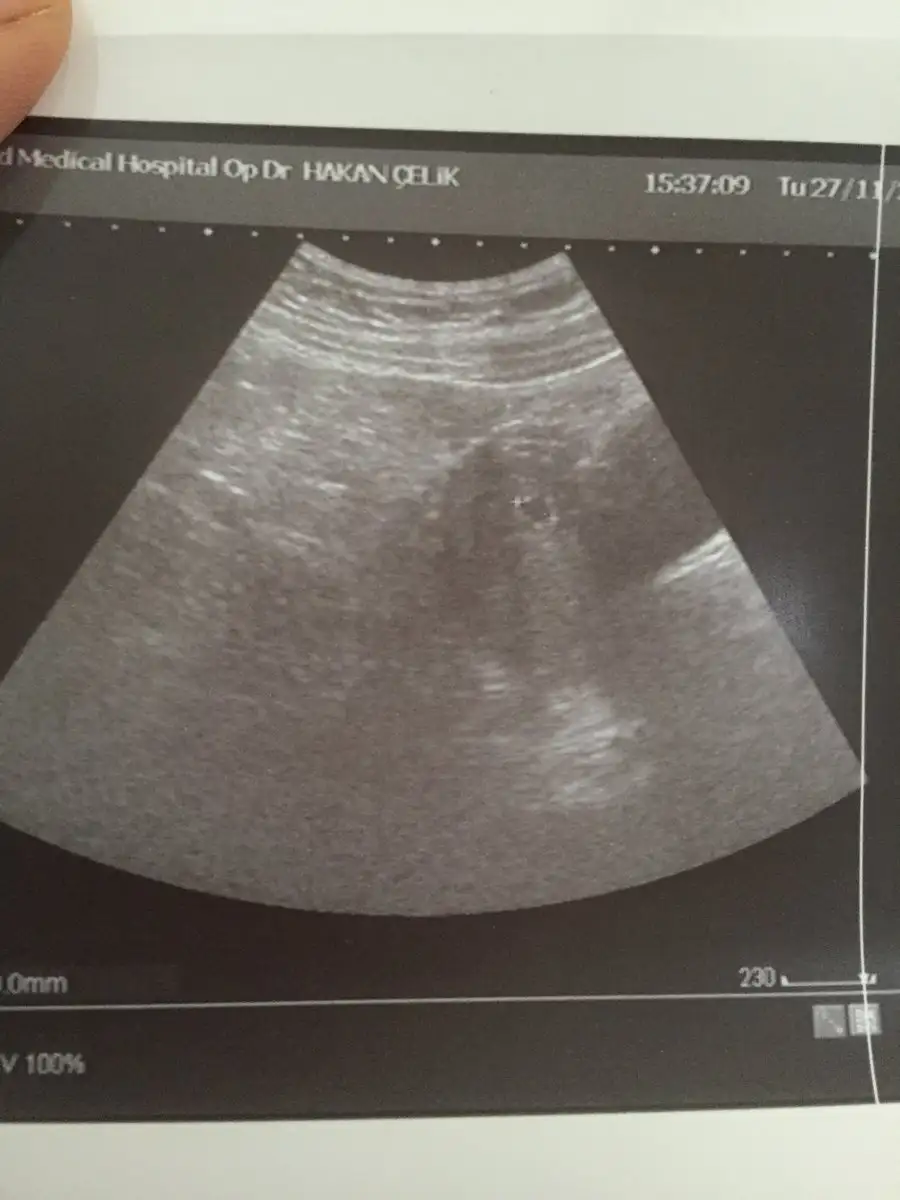

Merhaba kizlar bu gün kesem gözüktü 4+6 dedi doktor burdan biri kese hangi taraftaysa ona göre cinsiyet tahmin ediyordu kimdi o

• 561EC29F-59CA-4966-A730-A51A0998CE40.webp

561EC29F-59CA-4966-A730-A51A0998CE40.webp

42,8 KB · Görüntüleme: 50